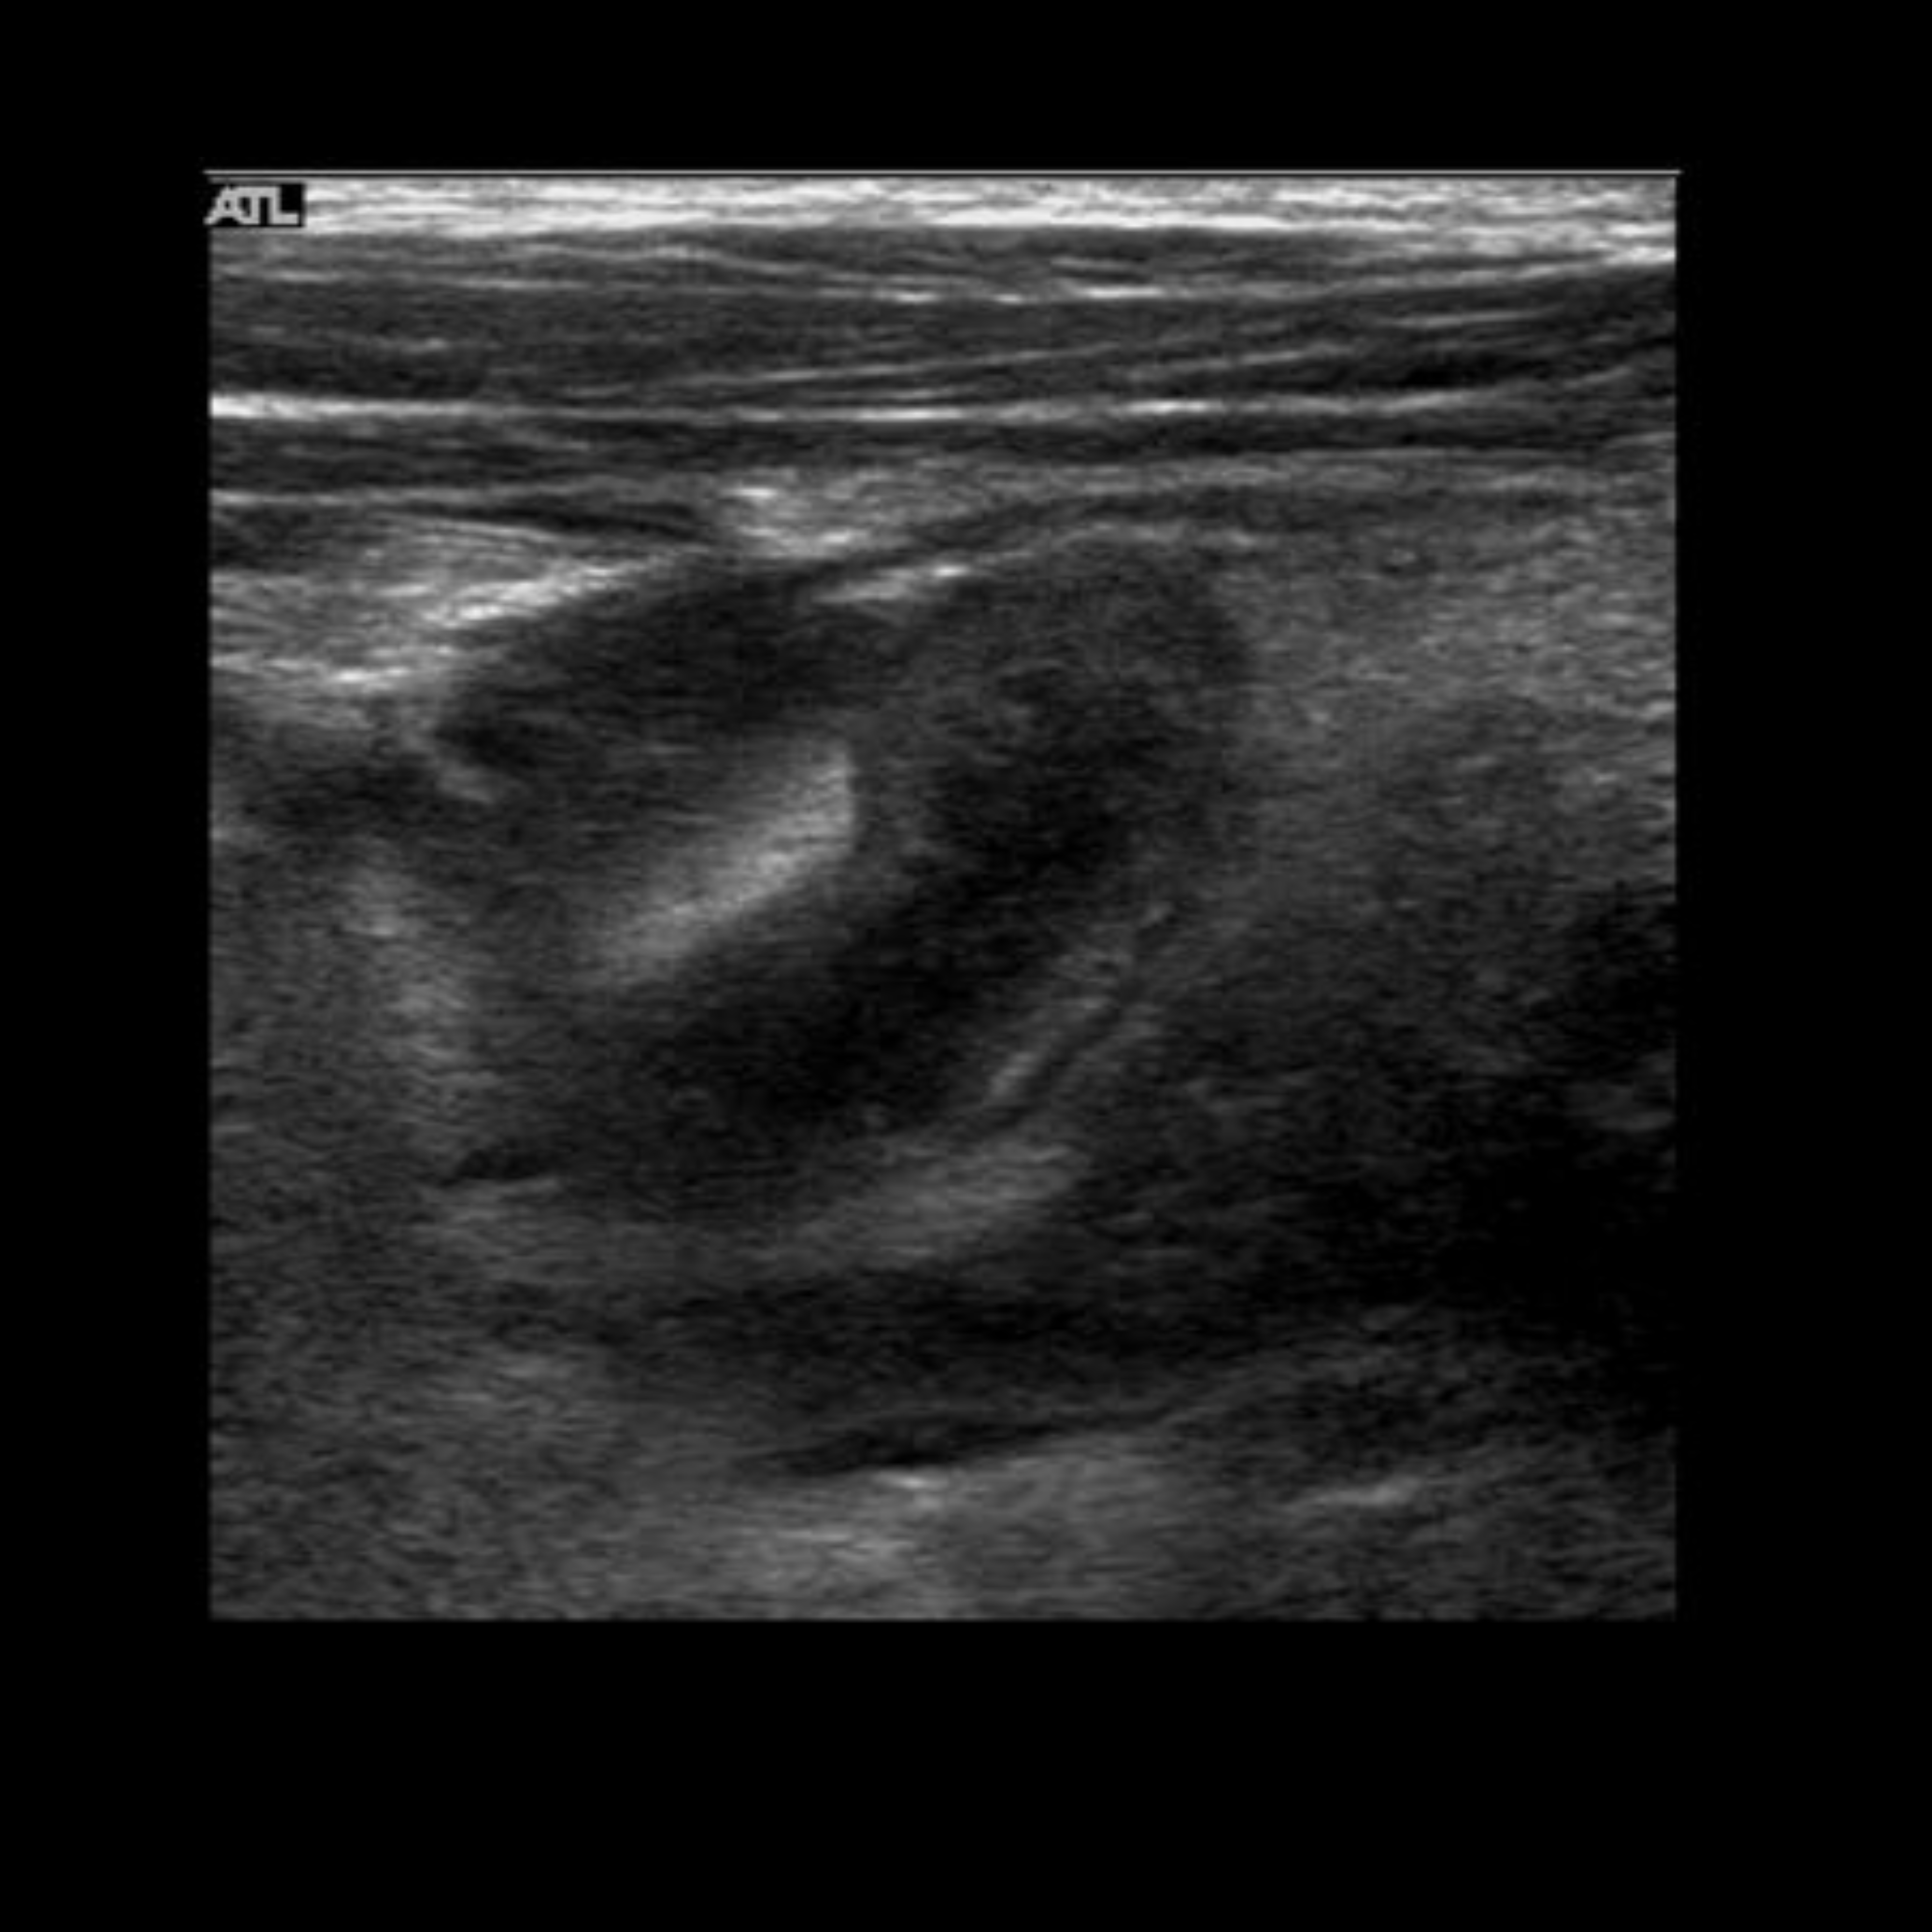

Appendicitis 6

Perforated appendicitis with complex fluid/abscess formation.